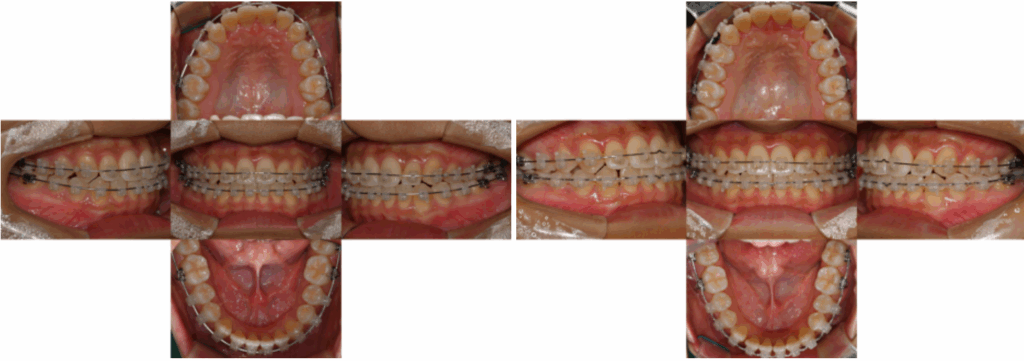

촬영일 : 24.04.30/24.05.29

앞니 배열 정리와

부분적 반대교합이 개선,

턱 끝 돌출감을 완화하면서

촬영일 : 24.10.07

정중선과 정렬 유지 및 교합 안정화를

진행해 드리기로 했습니다.